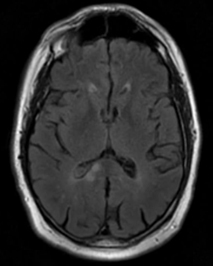

• Patient âgé de 61 ans adressé en juin 2013 pour infarctus cérébraux récidivants.

- 1er épisode (février 2012) : hémiparésie gauche révélant un infarctus du corps calleux à droite. Traitement par aspirine après un bilan étiologique négatif (ETT/ETO, Holter ECG des 24h, exploration des TSA, bilan immunologique, VIH, TPHA-VDRL).

- 2nd épisode (septembre 2012) : récidive d’hémiparésie gauche, une nouvelle IRM montre des lésions récentes ischémiques dans différents territoires vasculaires. Traitement anticoagulant dans l’hypothèse d’une origine cardio-embolique.